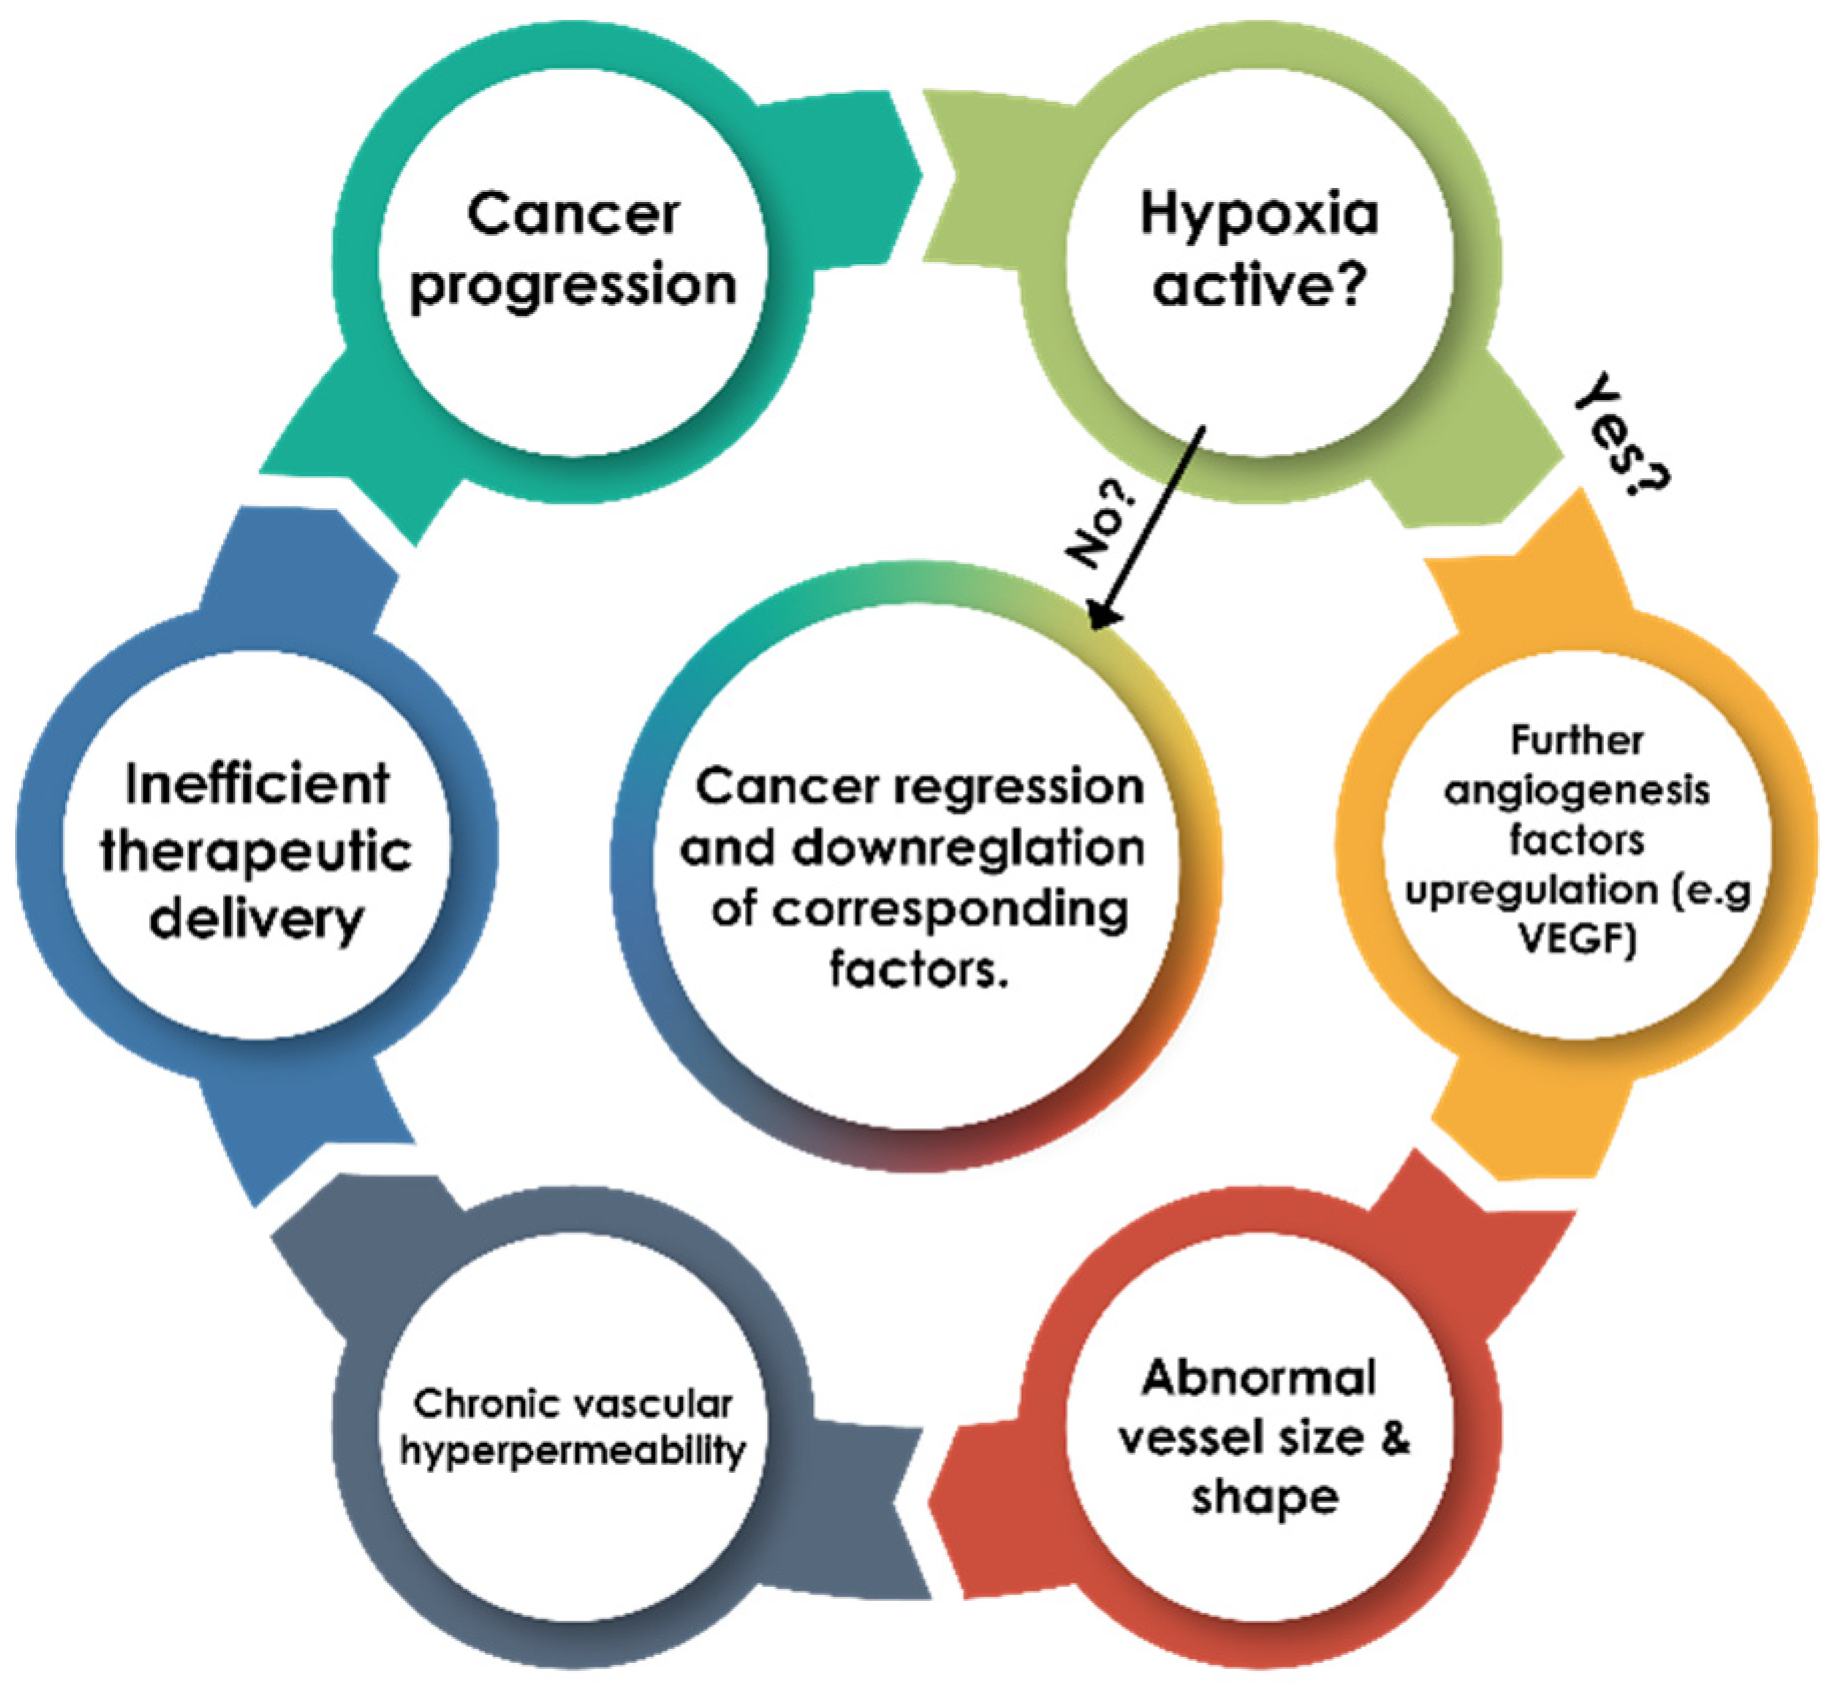

3.1. Hypoxia as a Limiting Factor for Cancer Therapeutics

3.2. Molecular Mechanisms of Cancer Resistance to Radiotherapy and Chemotherapy